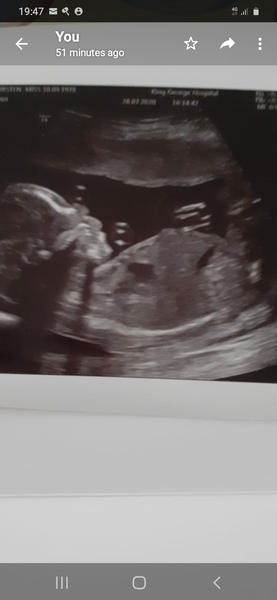

Kj1010 · 28/07/2020 19:50

@champoopapi this little bean

👣 Due Nov/Dec 👣 it's the 20 week scans! 👣

@Kj1010 yay! Gorgeous cutie 😍

How gorgeous @Kj1010 💙❤️💓